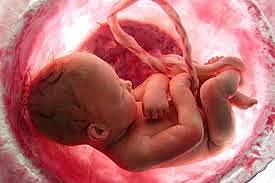

Desarrollo fetal

• Semana 8

22

Semana 8

los párpados están más desarrollados

las características externas del oído comienzan a tomar su forma final.

continúa el desarrollo de las características faciales

los intestinos rotan